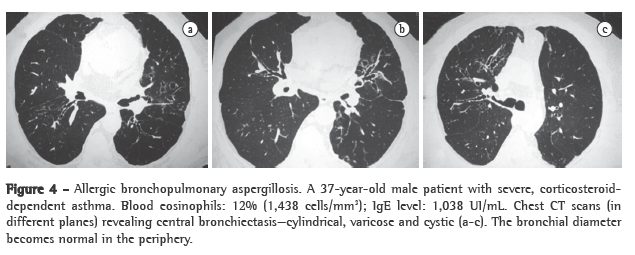

Bronchiectasis is defined as central when it is found in the medial two thirds and the bronchial diameter normalizes in the periphery.(36) It can be cylindrical, varicose or cystic (Figure 4). Expansion to the periphery in some areas or segments can occur in up to 30% of patients. In asthma patients, V- or Y-shaped opacities can indicate mucoid impaction and are suggestive of ABPA.(42,43) Mucoid impaction is defined as highly attenuated when the mucus density is higher than the skeletal muscle density.(41,44) High-attenuation mucoid impaction is also pathognomonic of ABPA and was seen in 29 (18.7%) of the 155 patients evaluated in another study.(44) Such impaction is attributed to the presence of calcium salts, metals (iron and magnesium) or products of hemorrhage in the impacted mucus. It is the same base as that of the finding of fungal sinusitis. In asthma patients, pulmonary infiltrates with foci of consolidation raise the possibility of ABPA.

The following criteria are considered essential for a diagnosis of ABPA: asthma with central bronchiectasis or pulmonary infiltrates; positive skin test reactivity to Aspergillus sp.; total IgE levels greater than 1,000 U/L; and IgE or IgG against Aspergillus sp. in the blood. Criteria that are not essential but confirm the diagnosis include eosinophilia and serum precipitins to (antibodies against) Aspergillus sp. The finding of Aspergillus sp. in sputum is of value only when accompanying the essential criteria. The fungus, which is extremely common, can be inhaled and eliminated in the sputum without causing disease. Certain tests are used as a means of screening for ABPA. Positive results on these tests do not confirm the disease, although negative results rule it out. The skin test is the most important of such tests, followed by determination of total IgE levels. Negative skin test results or low IgE levels in symptomatic patients excludes the diagnosis.(1) Asthma with central bronchiectasis and skin test reactivity to Aspergillus sp. are accepted as the minimum criteria.(42)